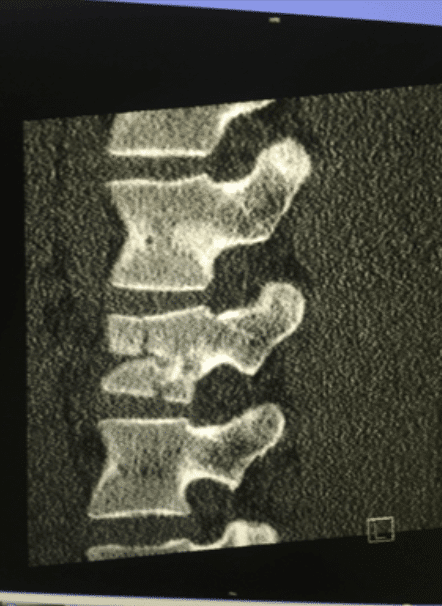

Goerke crashed while jumping through a large triple section and landed extremely short on the jump. The impact of the crash caused the majority of his injuries, fracturing his spine at the L2 vertebrae and broke his left clavicle. He was taken to Klinikum Chemnitz; a local hospital near the Fair where surgeons performed the first of two scheduled surgeries stabilizing his spine with rods. The second surgery to address the left clavicle break is expected to be scheduled this Thursday.